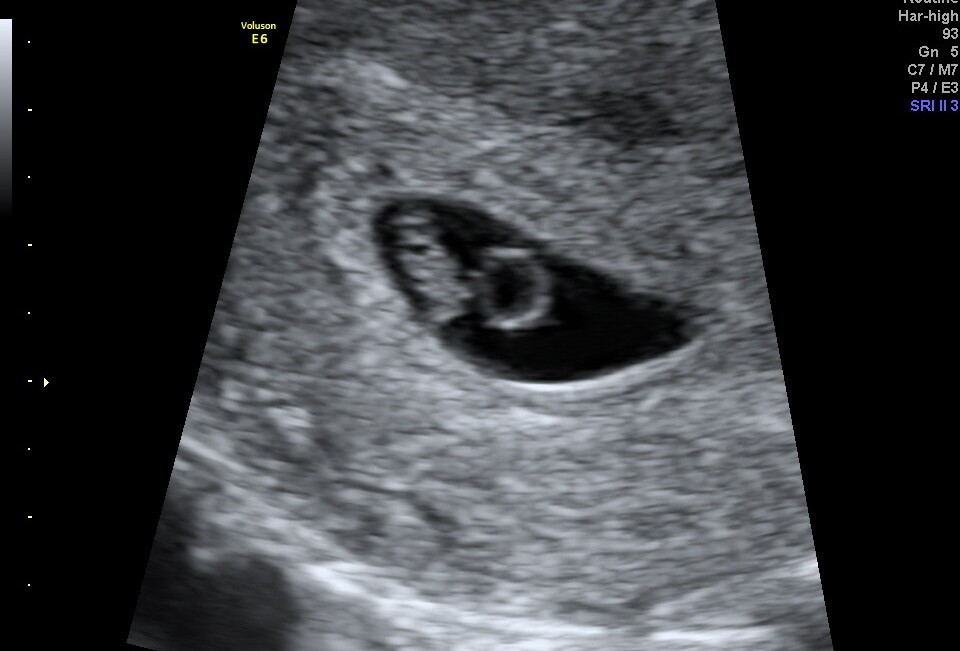

Hej, ja również po wizycie. Fasolinda urosła, serce bije pani doktor założyła kartę ciąży, wypisała skierowania na badania i zaprosiła na następną wizytę 13 sierpnia. Jeśli termin porodu by się sprawdził to będzie moje 3 dziecko urodzone 22 dnia tylko każde innego miesiąca :D

Załączniki

• IMG_20250730_213337.jpg

IMG_20250730_213337.jpg

690,5 KB · Wyświetleń: 46